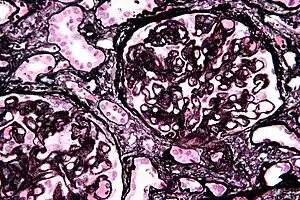

| Micrograph of membranous nephropathy showing prominent glomerular basement membrane spikes. Jones' stain. | |

- By light microscopy, the basement membrane is observed to be diffusely thickened. Using Jones' stain, the GBM appears to have a "spiked" or "holey" appearance.